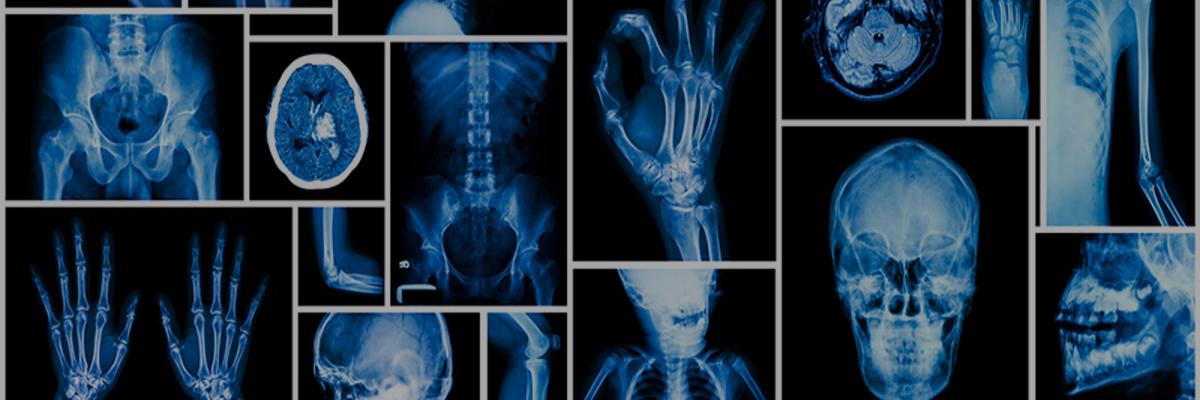

Es la persona que entra en mi consulta con un carrito de la compra llenos de informes, radiografías, resonancias magnéticas y scanners, densitometrías, podometrías y otras tantas fias...